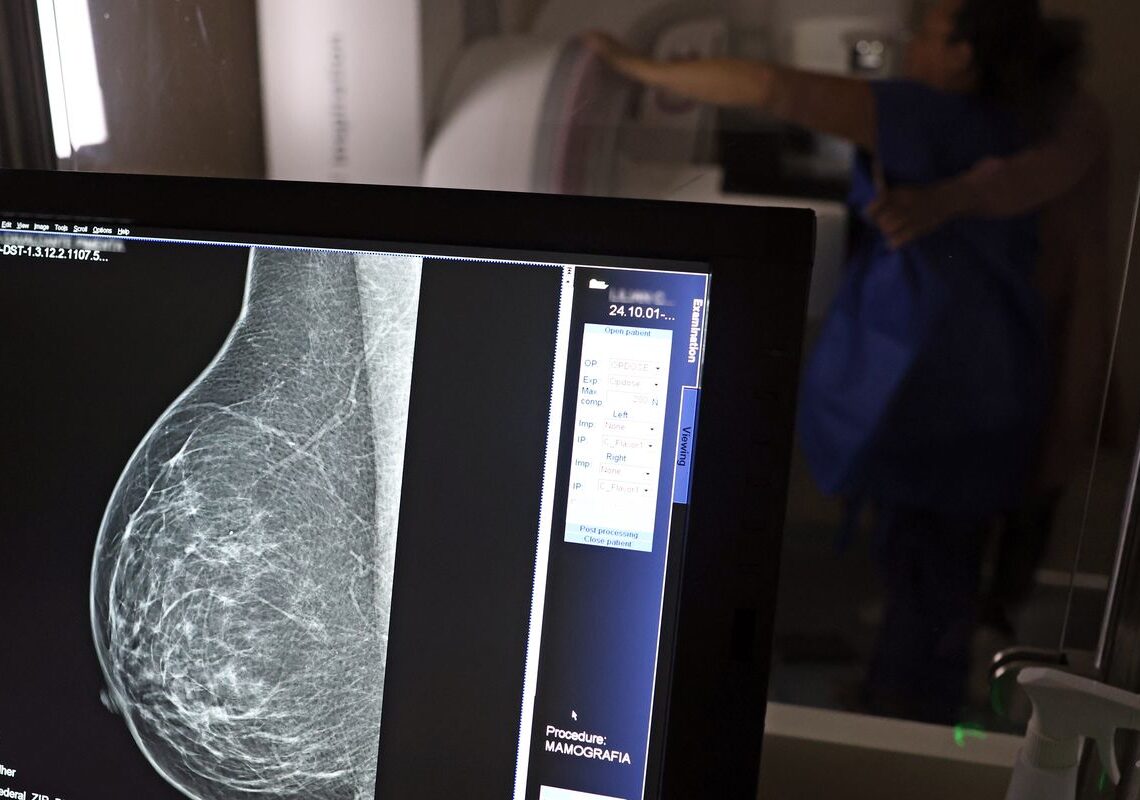

Em setembro, o Ministério da Saúde ampliou as diretrizes de rastreamento, recomendando que mulheres entre 40 e 49 anos realizem mamografias, mesmo sem sintomas. De acordo com o Instituto Nacional do Câncer (Imca), mais de 73 mil mulheres recebem o diagnóstico de câncer de mama anualmente no Brasil.

“O que é efetivo na redução da mortalidade é você descobrir o tumor antes de ter sintoma clínico. Quanto menor o tumor, melhor para a gente descobrir o tratamento e maior a chance de cura. E a gente só consegue fazer isso com exames de imagem”, diz Ivie.

Ela explica que no caso de diagnóstico de um câncer de mama com menos de 1 cm, a chance de cura é de 95% em cinco anos, independentemente se ele é do tipo mais agressivo. “E esses tumores só vão ser detectados na mamografia. Essas pessoas que têm que ir fazer mamografia são mulheres saudáveis. Não são mulheres doentes”, acrescenta.